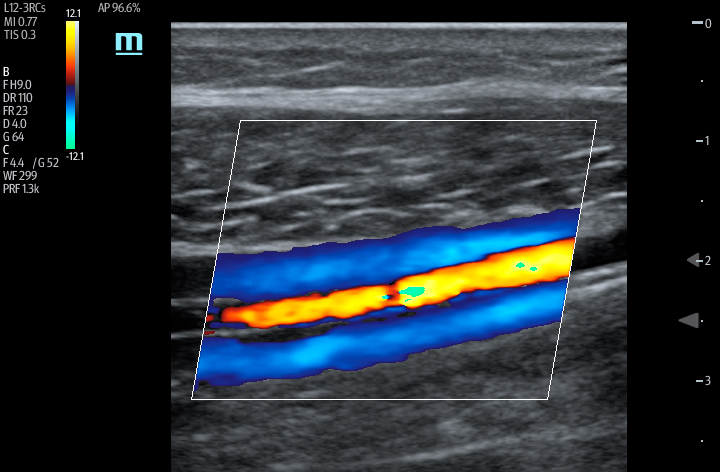

The TE7 Ultrasound System Crystal Series 2.0 is the system of choice from routine point-of-care exams to extreme situations when every second counts. With best-in-class image quality, a sleek form factor, and breakthrough needle visualization advancements, the TE7 System is designed to provide superior performance for rapid, confident exams and procedures in the fast paced, point of care environment.

Automated measurement of the Velocity Time Integral (VTI) and Cardiac Output (CO), enables rapid assessment of cardiac function. This software automatically locates color box and Pulse Wave Doppler (PW) sample line in real time. A graph of parameter trends for CO, Stroke Volume (SV) and VTI is produced to guide decision-making.